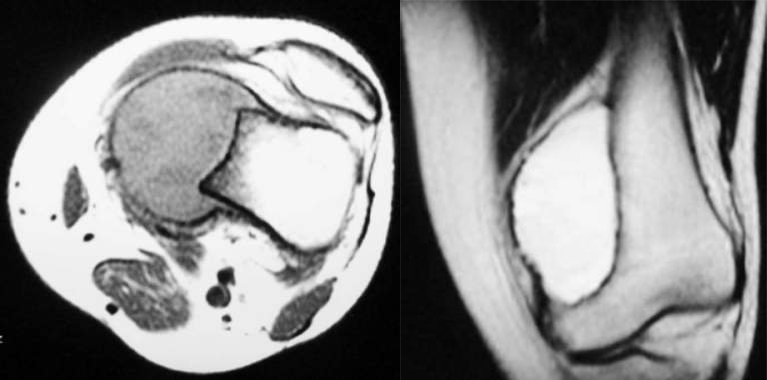

CASE 1男性,23 岁,主诉:右小腿上段疼痛伴右膝关节肿胀 2 月余

378e3adfddcb4fd88a7dac9006626939.png

f0c75cbf4ac005bdf44c1a191c0ff29c.png

免疫组化结果:右胫骨肿瘤,骨巨细胞瘤。

CT 示膨胀性骨质破坏,病变偏心,病变位于皮质内,呈气球样突出,病变被包绕于相对连续的骨膜新骨内

MRI 示:病灶于 T1WI 为中等不均匀信号,未见分隔;T2WI 为高信号。可见边缘连续的骨壳